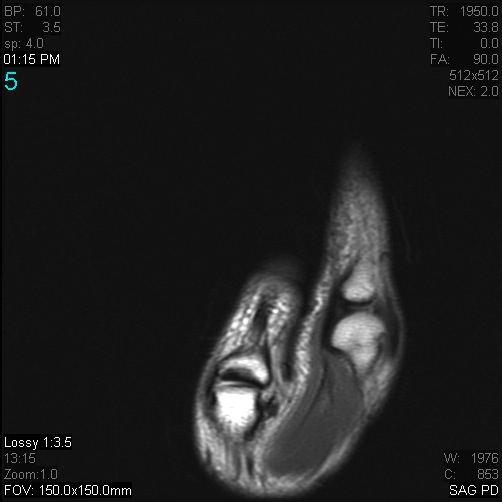

Figure 3 for case Stener lesion

Figure 3